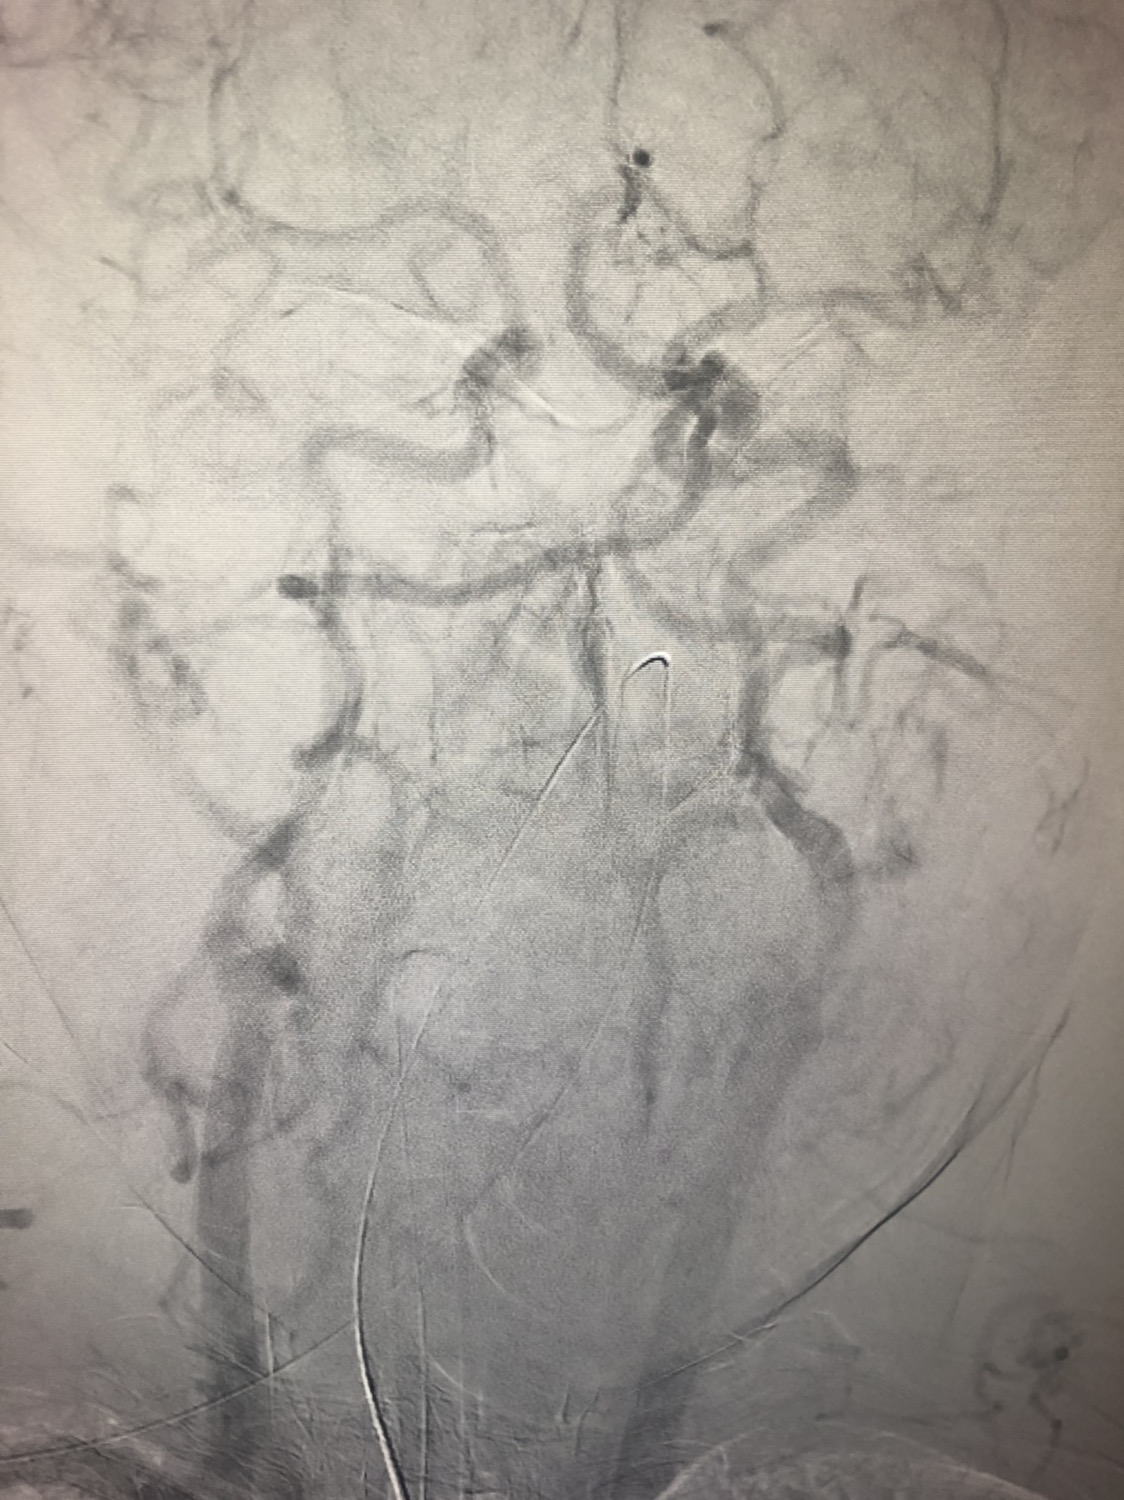

1周前房颤栓塞肱动脉,切开取栓后服用利伐沙班3天。突发偏瘫凝视3小时。上台看M3、A3血栓,国产普威森6f125cm抽吸导管高到位结合尼科3x20mm小支架,结合精细操作,m3和a3的血栓也可以轻松取出。不刺激血管。加造影射线16min两次取栓两个血管再通。

柔软的国产普威森微导管,高到位。

3x20mm的国产reco支架,适合分支血管取栓。